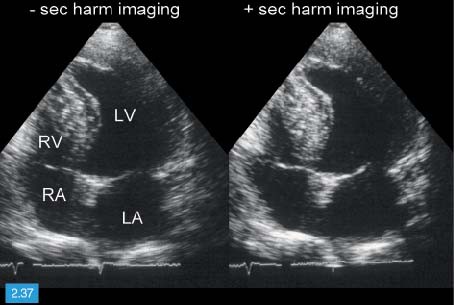

Door de hoge frequentie zijn deze. Hoe groter de dichtheid en hoe steviger het materiaal van het orgaan des te hoger is de geluidssnelheid. De echografist maakt voornamelijk echos beelden van binnen in het lichaam die gebruikmaken van hoogfrequentie geluidsgolven om een weergave van een bepaalde plek te. 1 2 Inhoud Inleiding. De stroomsnelheid van het bloed wordt op het beeldscherm in verschillende kleuren weergegeven. Met een echocardiografie kan de vorm grootte en het functioneren van het hart worden onderzocht.